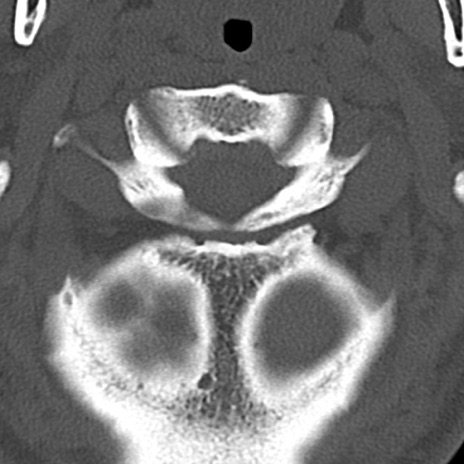

頚椎CT

横断像